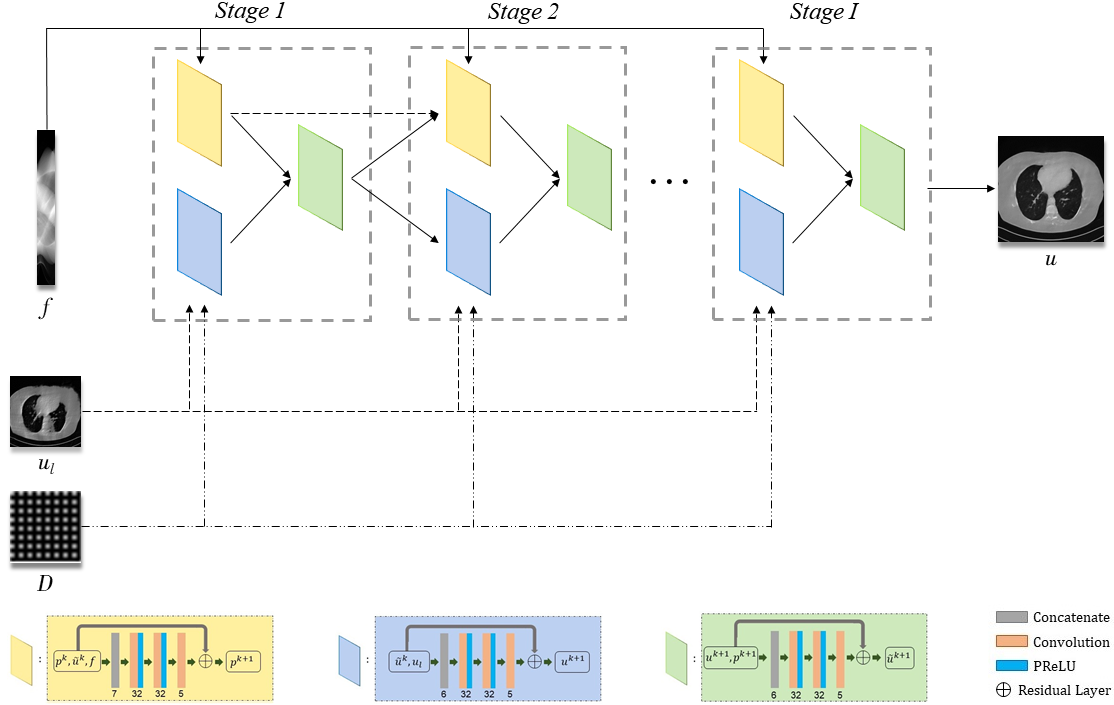

The unrolling strategy is a discriminative learning method by unrolling an iterative optimization algorithm into a hierarchical architecture. Fig. 1 depicts the network structures of low-resolution reconstruction model, we use the classical learned primal-dual reconstruction method [22] to obtain the low-resolution solution , for which we can also adopt other advanced learning-based methods or variational methods. Fig. 2 depicts the network structures of our LRIP-net, which has three inputs including the incomplete projection data , the system matrix , and the reconstructed low-resolution image . More specifically, there are three blocks in each stage of the high-resolution reconstruction, which correspond to the three variables. As shown at the bottom of Fig. 2, each block involves a 3-layer network.

The total depth of the network depends on the number of stages contained in the network, which is chosen to balance the receptive fields and the total number of parameters. The proposed network introduces the residual structure for two reasons: 1) the residual structure makes the network easier to train and optimize because each update is only a small offset, and 2) the skip connections can alleviate gradient disappearance and gradient explosion caused by increasing the depth of deep neural networks. The non-linear activation functions are chosen as the Parametric Rectified Linear Units (PReLU) function. As displayed in Fig. 2, we set the numbers of channels in each stage as for , for and , where the differences in the numbers are due to the dimension of inputs. The convolutions are set to be of the size in our network. Furthermore, we choose the Xavier initialization scheme for the convolution parameters and the zero initialization for all biases. The convolution stride is set as 1 and the padding strategy is chosen as ‘SAME’ in the network.